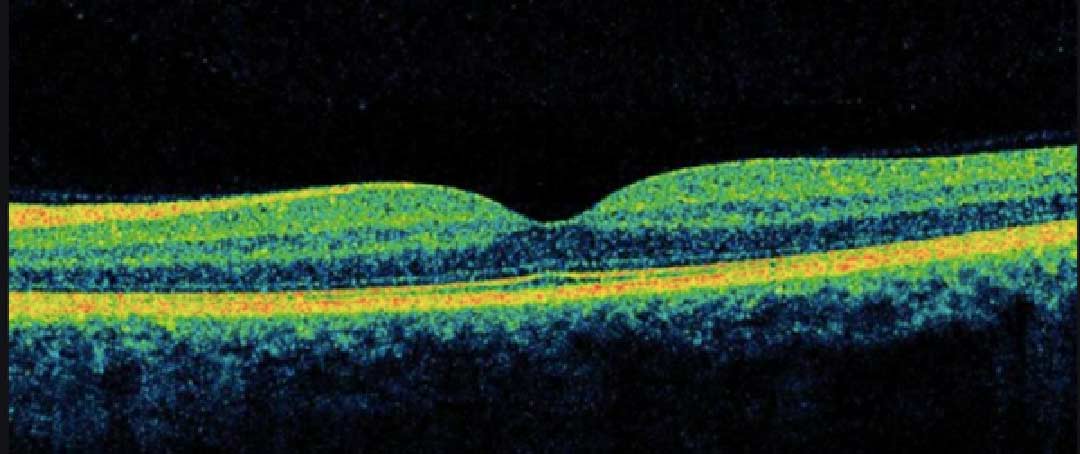

The centre of eyesight located on the retina called macular

Macular hole is a disease that is caused by a hole at the centre of the eye.

Refer below picture to understand more :

One possible risk factor is a condition called vitreomacular traction. As you get older, the vitreous jelly in the middle of your eye starts to pull away from the retina and macula at the back of the eye. If some of the vitreous jelly remains attached, it can lead to a macular hole.